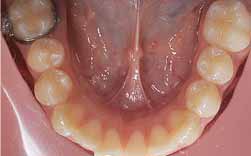

A perda de um molar de leite deve ser de imediato compensada com um dispositivo mantedor do espaço.

Quando a perda já se verifica e o exames demonstram a existência de falta de espaço para a erupção dever-se-à recorrer a um dispositivo apropriado para a recuperação do mesmo.